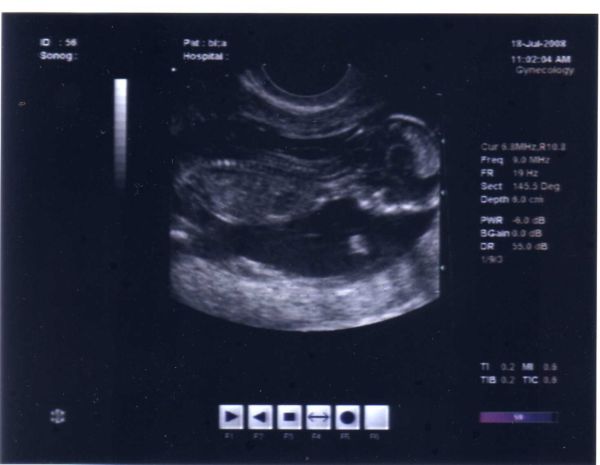

A súlybecslés az UH alapján viszont igen: már 1 hónappal a gyerekek születése előtt jelezték, hogy nem lesznek kicsik... sőt, a fiamnál 1 héttel a születése előtt 150 grammal kevesebbet mondtak, mint amivel végül megszületett, de nyilván orvosfüggő.

Erzsébet, neked is a szép babóhoz, Móni: nagyon jó az a kép, hihetetlen, hogy látszik minden kis csigolyája

20080718uh [/img]

20080718uh [/img]